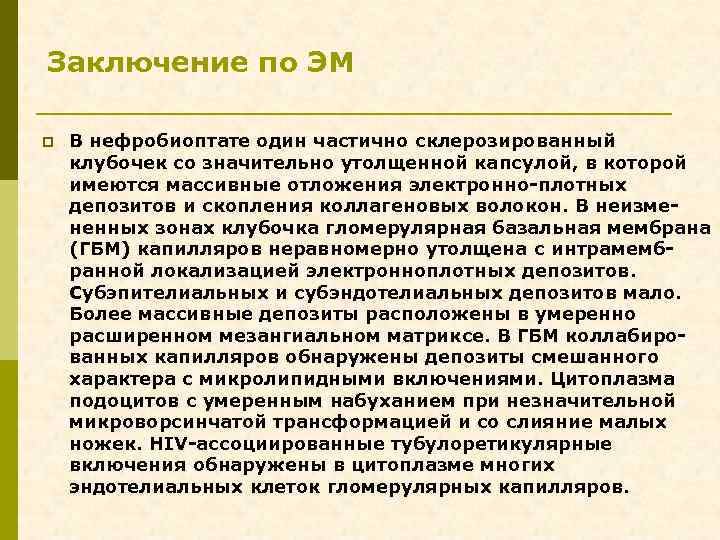

Заключение по ЭМ p В нефробиоптате один частично склерозированный клубочек со значительно утолщенной капсулой, в которой имеются массивные отложения электронно-плотных депозитов и скопления коллагеновых волокон. В неизмененных зонах клубочка гломерулярная базальная мембрана (ГБМ) капилляров неравномерно утолщена с интрамембранной локализацией электронноплотных депозитов. Субэпителиальных и субэндотелиальных депозитов мало. Более массивные депозиты расположены в умеренно расширенном мезангиальном матриксе. В ГБМ коллабированных капилляров обнаружены депозиты смешанного характера с микролипидными включениями. Цитоплазма подоцитов с умеренным набуханием при незначительной микроворсинчатой трансформацией и со слияние малых ножек. HIV-ассоциированные тубулоретикулярные включения обнаружены в цитоплазме многих эндотелиальных клеток гломерулярных капилляров.